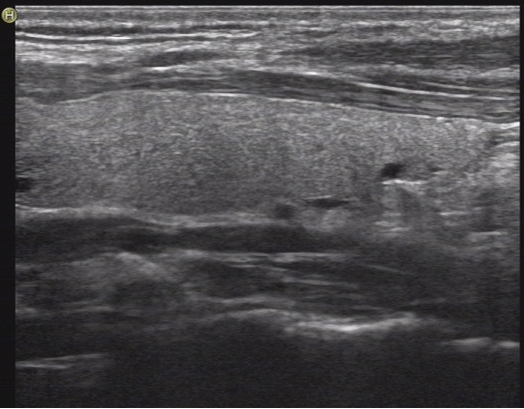

3.B超:表现为甲状腺体积增大,弥漫性低回声,不均质改变,典型的出现“网格征”,见下图:

图1 正常甲状腺超声的表现,腺体均匀。

图2 慢性甲状腺炎的表现,腺体可见很多小黑片状区域,呈网格状。